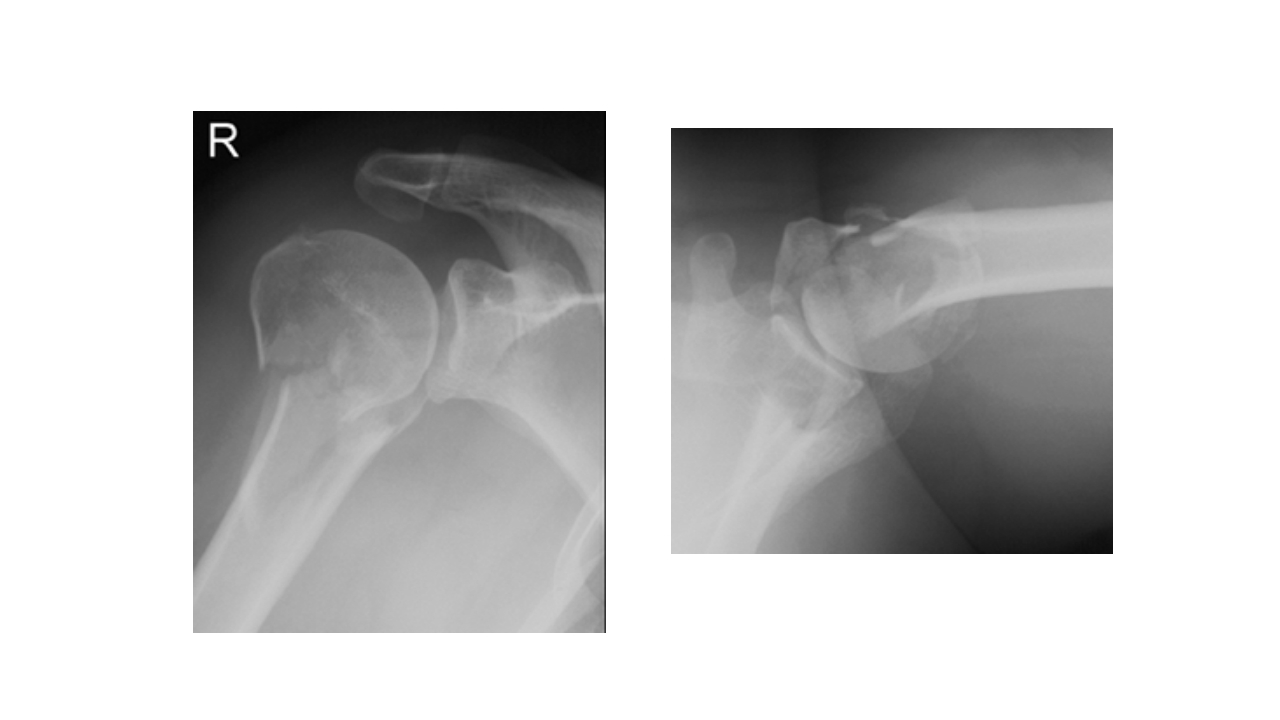

BUSINESS REPORT 肱骨外科颈骨折 汇报人:XXX 202X 汇报时间: 一 病史 主 二 解剖 要 三 病因 四 诊断和鉴别诊断 内 五 并发症 容 六 治疗 七 洗手巡回配合 (一) 病史 XXX,女,65岁,骨一科,+8床,391109,患者自诉不慎跌倒致 左肩部外伤疼痛,肿胀,活动受限,休息后无缓解,现来我院摄 X线片示:左肱骨外科颈骨折,予以收住入院。病程中无昏迷、 呕吐、畏寒发热。无逆行性遗忘。 (一) 病史 体温 36.4℃ 脉搏 76次/分 呼吸 20次/分 血压 100/80mmHg 一般情况 发育正常,营养良好,体型正常,神志清楚。皮肤、 粘膜温度正常,干燥,未见黄疸、皮疹或出血点。 患者于2012年10月8日9:00在臂丛神经阻滞麻醉下行左肱骨外科 颈切开复位内固定术,手术顺利,于10:...